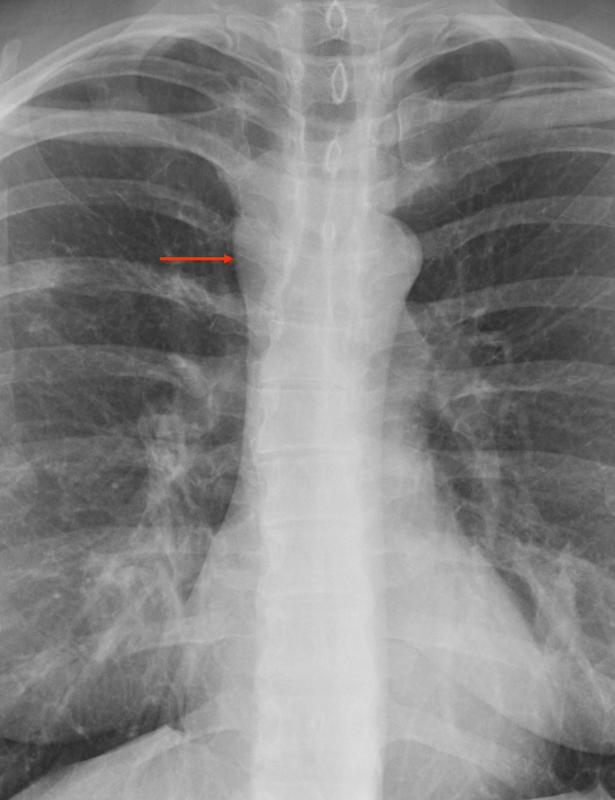

Foregut cyst (and RML pneumonia)

Foregut cyst

(and RML pneumonia)